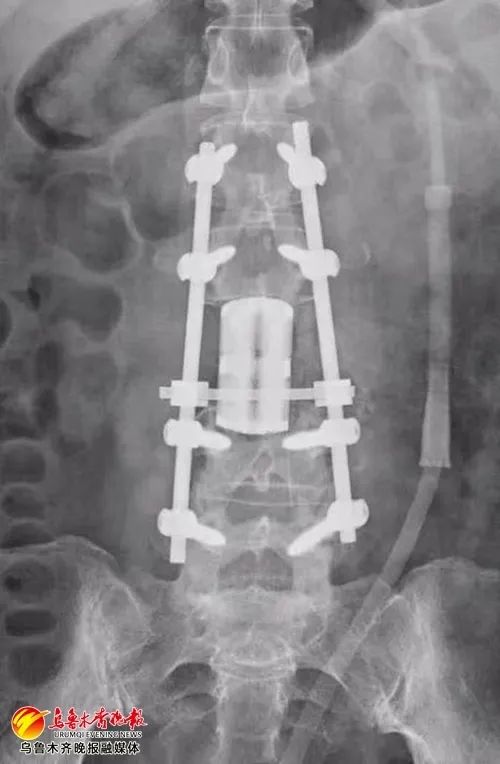

单女士做完3D打印人工椎体置换术后的X线影像资料

3D打印的人工椎体具有组织相容性好、耐磨、寿命长的特性。历时10个小时手术,3D打印人工椎体被成功植入单女士体内,放置位置精准,与周围组织结构契合牢固,手术顺利完成。3D打印人工椎体完美契合了上下正常椎体的连接面,其3D多孔钛合金打印设计为人工椎体提供了足够的生物力学强度,增加人工椎体的稳定性。